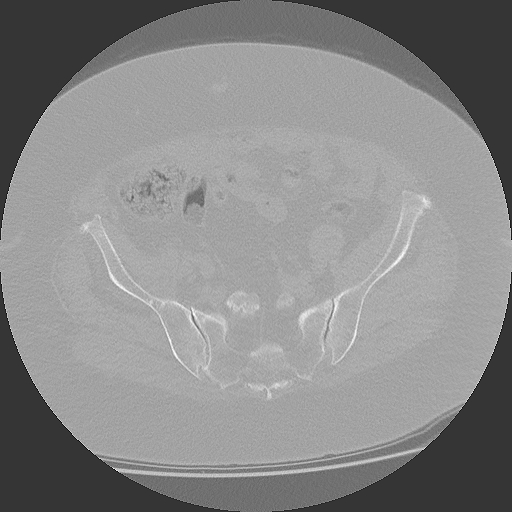

04.03.2025

CT Becken mit Radiologiebefund

DICOM PDF

Aktuelles CT des Beckens mit schriftlichem Befund.

CT Becken

853 Bilder in 4 Serien | 86 MB

4 Serien verfügbar

März 2025

CT Becken + Überweisung

CT-Untersuchung mit Befund, Überweisung zur weiteren Behandlung